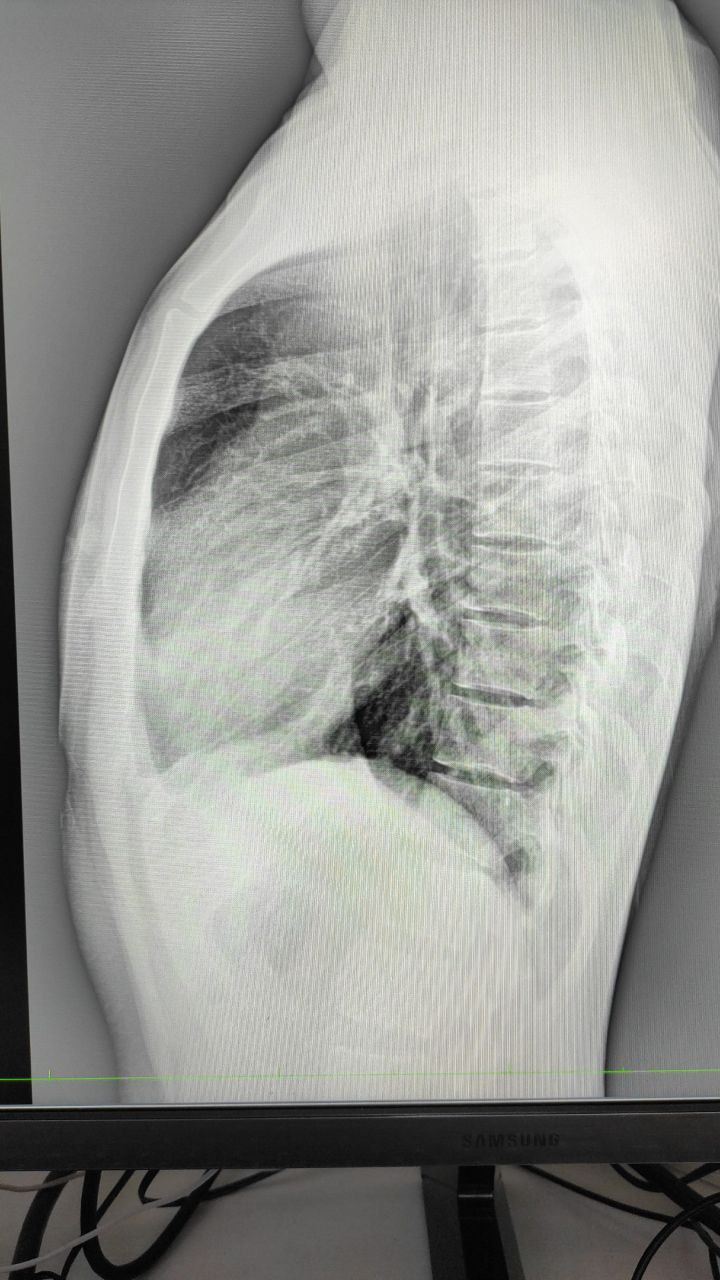

Доброй ночи. Анамнез неизвестен, жалоб нет

Какие мысли?